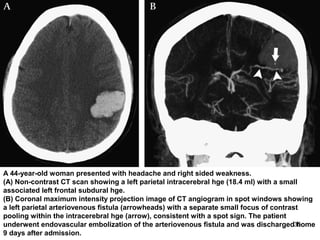

A 44-year-old woman presented with headache and right sided weakness.

(A) Non-contrast CT scan showing a left parietal intracerebral hge (18.4 ml) with a small

associated left frontal subdural hge.

(B) Coronal maximum intensity projection image of CT angiogram in spot windows showing

a left parietal arteriovenous fistula (arrowheads) with a separate small focus of contrast

pooling within the intracerebral hge (arrow), consistent with a spot sign. The patient

underwent endovascular embolization of the arteriovenous fistula and was discharged home

9 days after admission.